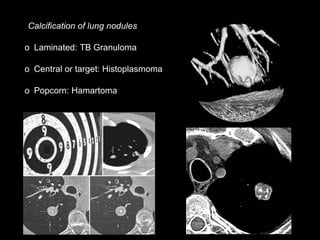

Calcification of lung nodules

o Laminated: TB Granuloma

o Central or target: Histoplasmoma

o Popcorn: Hamartoma